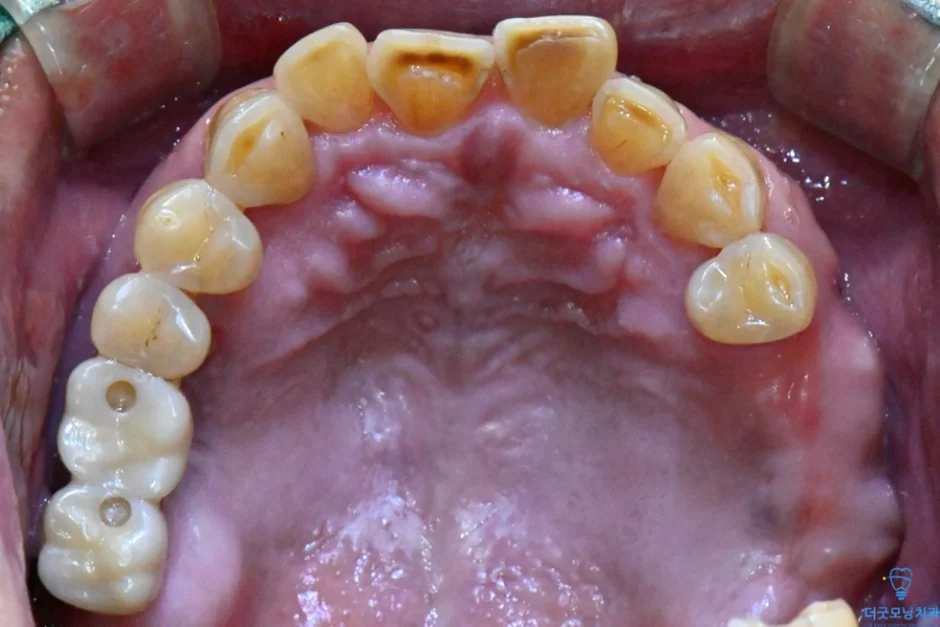

2. 검진 결과 — 파노라마 엑스레이 & CT 분석

먼저 파노라마 엑스레이와 CT를 통해 구강 전체 상태를 확인하였습니다.

■ 보철 마무리

양쪽 임플란트 식립이 완료된 후 보철 준비를 거쳐 최종 보철까지 마무리하였습니다.